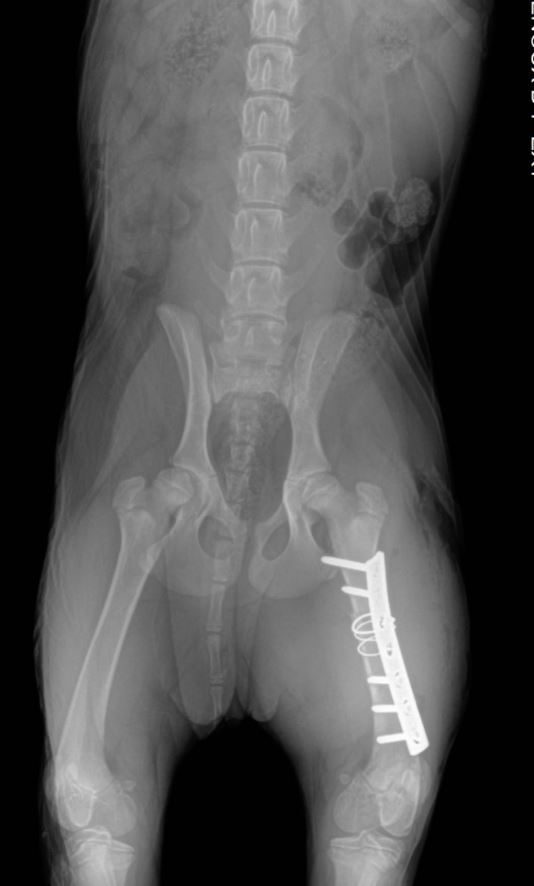

Chirurgies orthopediques:

-réduction des fractures (pose divers implants plaques broches etc),

-rupture du ligament croisé (prothèse ligamentaire)

Pose implant plaque DCP

Pose broche en "X" fracture femur en "Salter"